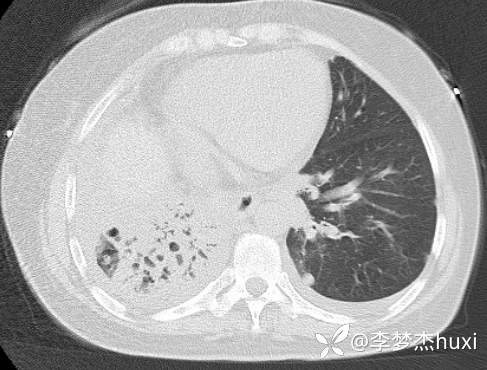

8.22治疗后的胸部CT: